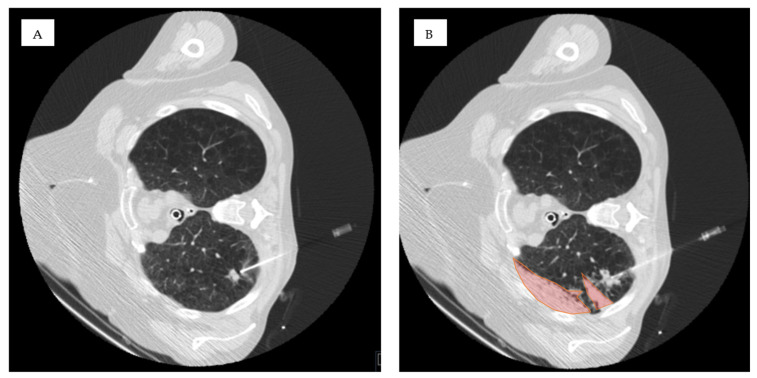

Background/objectives: The risk of hemorrhage during CT-guided lung biopsy has not been systematically studied in cases where ground-glass opacities (GGO) are present in the access route or when biopsies are performed in highly perfused, dependent lung areas. While patient positioning has been studied for pneumothorax prevention, its role in minimizing hemorrhage risk remains unexplored. This study aimed to determine whether GGOs in the access route and biopsies in dependent lung areas are risk factors for pulmonary hemorrhage during CT-guided lung biopsy.

Methods: A retrospective analysis was conducted on 115 CT-guided lung biopsies performed at a single center (2020-2023). Patients were categorized based on post-interventional hemorrhage exceeding 2 cm (Grade 2 or higher). We evaluated the presence of GGOs in the access route and biopsy location (dependent vs. non-dependent areas) using chi square, Fisher's exact, and Mann-Whitney U tests. Univariate and multivariate logistic regression analyses were conducted to evaluate risk factors for pulmonary hemorrhage.

Results: Pulmonary hemorrhage beyond 2 cm occurred in 30 of 115 patients (26%). GGOs in the access route were identified in 67% of these cases (p < 0.01), and hemorrhage occurred more frequently when biopsies were performed in dependent lung areas (63% vs. 40%, p = 0.03). Multivariable analysis showed that GGOs in the access route (OR 5.169, 95% CI 1.889-14.144, p = 0.001) and biopsies in dependent areas (OR 4.064, 95% CI 1.477-11.186, p < 0.001) independently increased hemorrhage risk.

Conclusions: GGOs in the access route and dependent lung area biopsies are independent risk factors for hemorrhage during CT-guided lung biopsy.